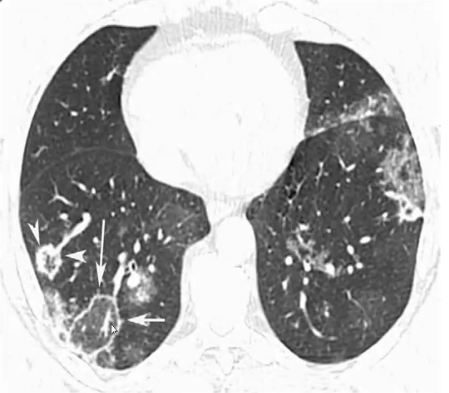

肺副球孢子菌病(Pulmonary paracoccidioidomycosis)

❖ RHS:中下肺野、多发、毛刺状边缘,同时伴有其它类型肺实质异常,考虑此病